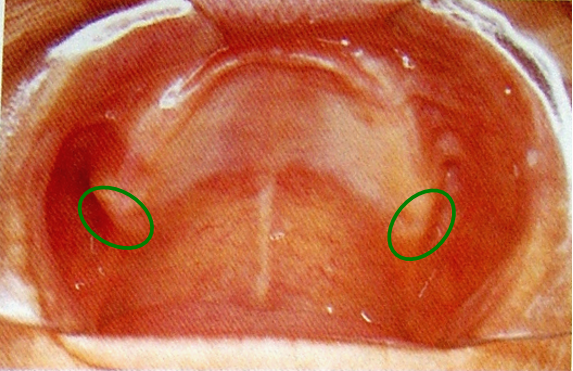

8.腭小凹(palatal fovea)

口内粘液腺导管的开口,位于上腭中缝后部的两侧。

上颌全口义齿的后缘应在腭小凹后2mm处 ,颤动线位于腭小凹的稍前部。